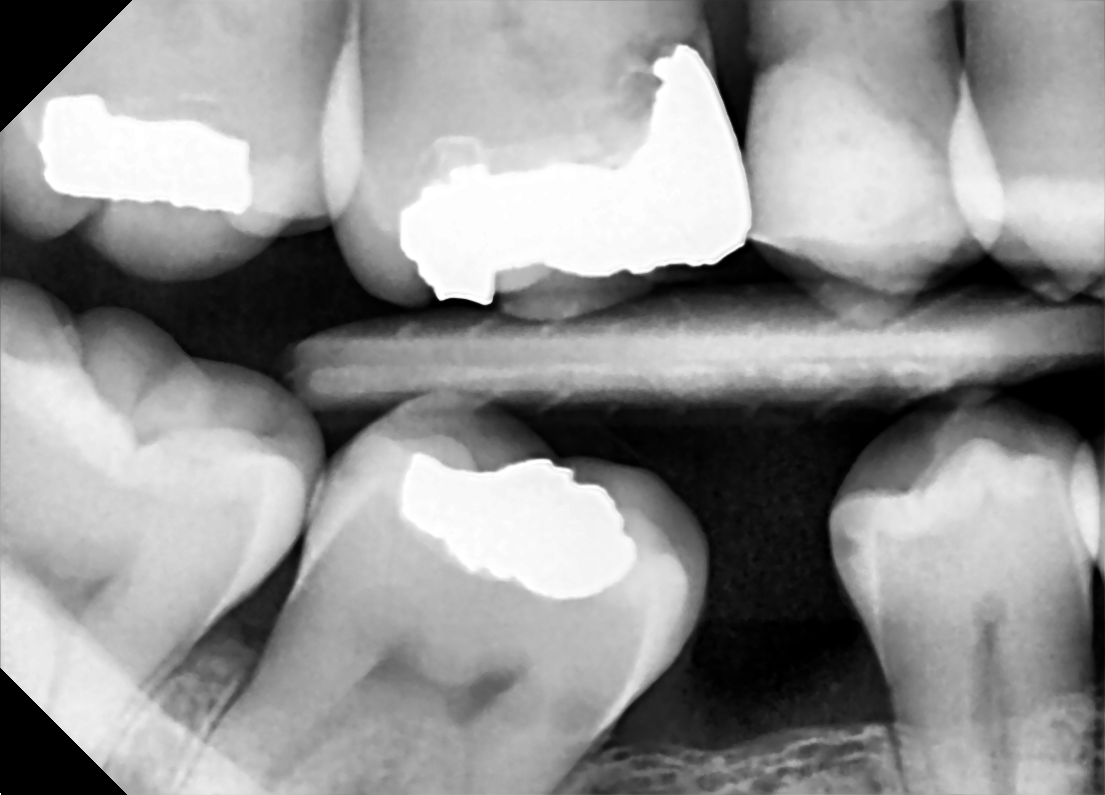

Ask The Dentist What Are Dental X Rays And Are They Safe Capstone Dental

Dental X Rays University Of Michigan School Of Dentistry